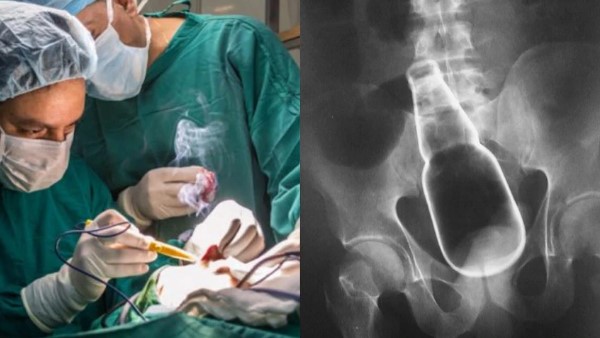

दरअसल, 29 साल के व्यक्ति ने नशे की हालत में मलाशय के रास्ते शराब की बोतल अंदर डाल ली थी। गुरुवार को को उसे पेट में तेज दर्द की शिकायत हुई, जिसके बाद उसे नागपट्टनम जिला अस्पताल में भर्ती कराया गया। डॉक्टरों ने सोनोग्राफी की, रिपोर्ट में डॉक्टरों ने पाया कि व्यक्ति के पेट में शराब की साबुत बोतल है, जिसे देखकर सभी हैरत में पड़ गए। डॉक्टरों ने 2 घंटे की लंबी सर्जरी के बाद उसके पेट से बोतल को निकाल दिया। डॉक्टरों के अनुसार मरीज की स्थिति अभी स्थिर बनी हुई है।

अस्पताल के सर्जन एस पांडियाराज के मुताबिक, युवक ने 26 मई को अपने रेक्टम में शराब की बोतल डाली थी। वह दर्द से परेशान था। शर्म की वजह से किसी को इस बारे में बताया भी नहीं।यहां तक कि अपने घरवालों को भी नहीं बताया था। जब दर्द बर्दाश्त से बाहर हो गया, तब घरवाले उसे अस्पताल लेकर आए। उन्होंने बताया कि युवक ने रेक्टम से बोतल निकालने का काफी प्रयास किया। इस प्रयास में बोतल बाहर निकलने की बजाय और अंदर बड़ी आंत तक पहुंच गई।

डॉ. पांडियाराज के मुताबिक, उन्होंने अपने जीवन में इस तरह का पहला केस देखा है। उन्होंने कहा कि अगर युवक की आंत में बोतल टूट जाती तो हमें एक एक टुकड़े को ऑपरेशन कर निकालना पड़ता और तब यह ऑपरेशन काफी जटिल हो जाता। युवक की करीब दो घंटे तक सर्जरी की गई और इस तरह सावधानीपूर्वक शराब के बोतल को बाहर निकाल दिया गया। उन्होंने मरीज की हालत अब स्थिर है। वह अभी भी दर्द महसूस कर रहा है पर जल्द ही उसके घाव भर जाएंगे।